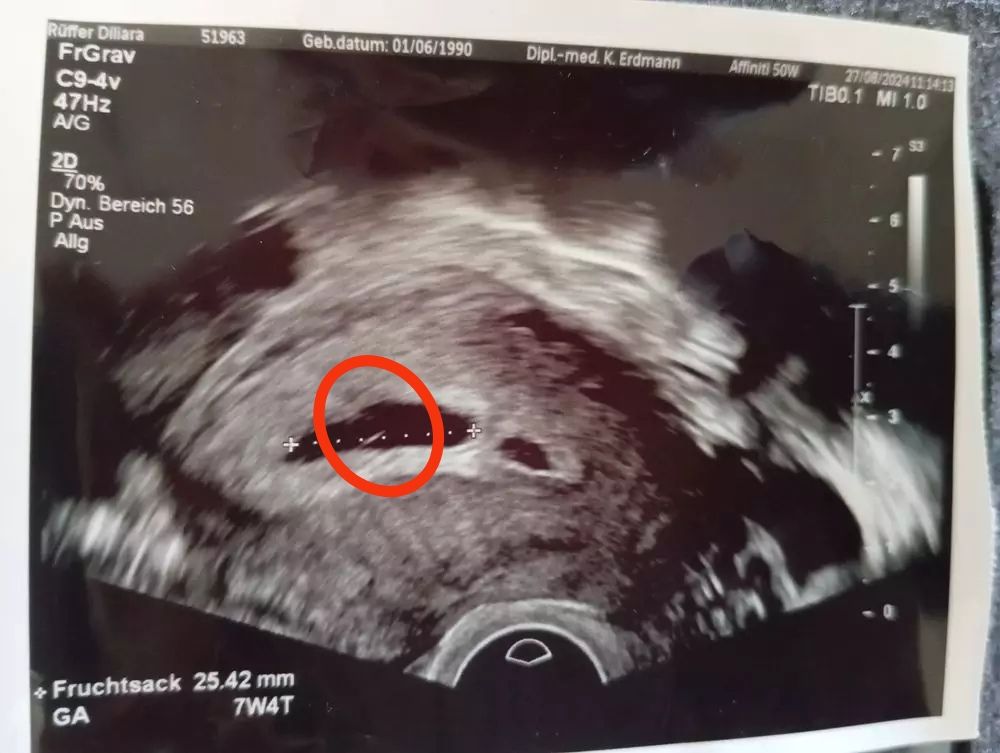

Вот на фото ваш желточный мешочек

А вот моя анэмбриония с желточным мешочком

Жм внутри есть у вас по фото,но он тоже не показатель,у меня анэмбриония с жм была, овуляция отслежена ровно на 14 д.ц была,хгч рос отлично и плодное яйцо росло хорошо,но эмбрион не появился

Но я как видите УЗИ несколько раз переделала,чтоб наверняка,пя росло отлично,но увы... В нормальную беременность в 6,1 пя 19,ктр 5,4 и ЧСС 146 уд/мин,в 8,0 пя 28 мм,ктр 18 и сб+ к сожалению если у вас срок по месячным 7,4 то пя соответствует сроку и в этом пя уже большой эмбрион должен быть,признаки сохраняются от растущего хгч,плодное яйцо растет и вырабатывает хгч